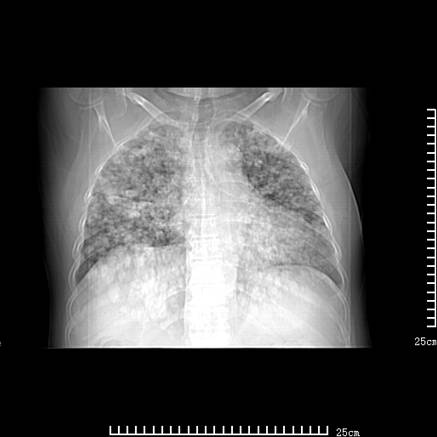

张男,75岁,干咳半年余,小便不利二年,b超检查前列腺增大,未见明显肿块;前列腺癌血生化检查多项指标明显增高。

双肺内多发转移瘤,纵膈淋巴结转移。来源前列腺?建议盆腔mri进一步检查。

双肺转移满了。

两肺广泛转移瘤。